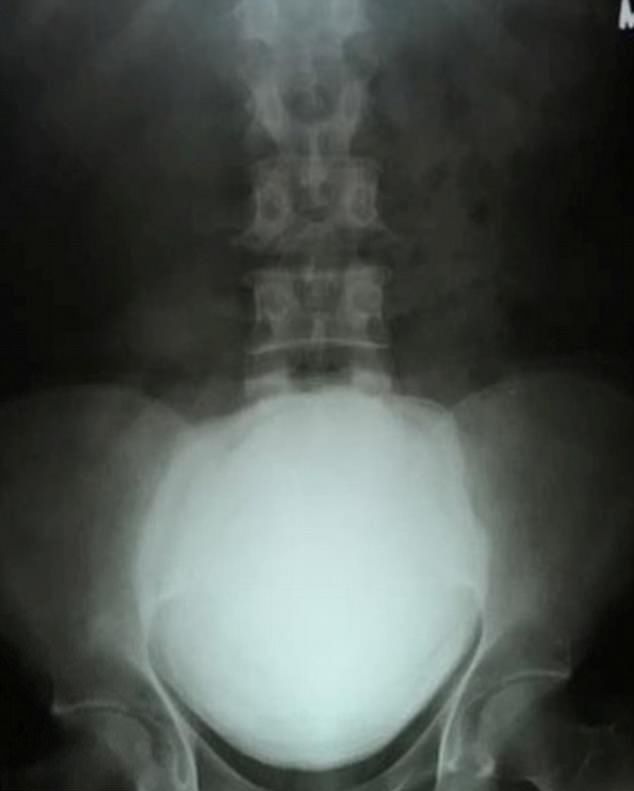

gif_animation おそらく「今まで発見された中でも最大級であろう」とされる尿路結石(膀胱結石)がインドの男性の体から摘出された。重さ1.4kg、恐ろしい痛み…。[6]img